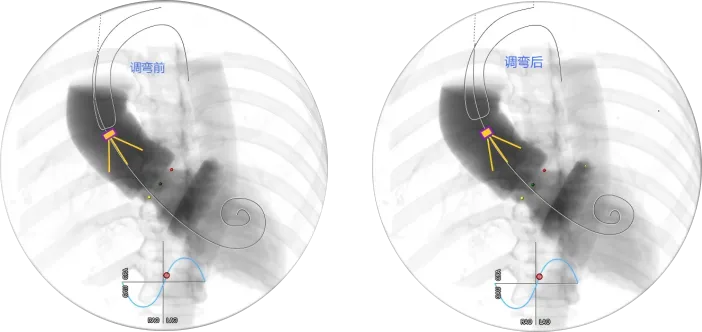

瓣膜调弯解离

瓣膜锚定键体位确认

瓣膜调弯后解离

定位键窦对齐验证